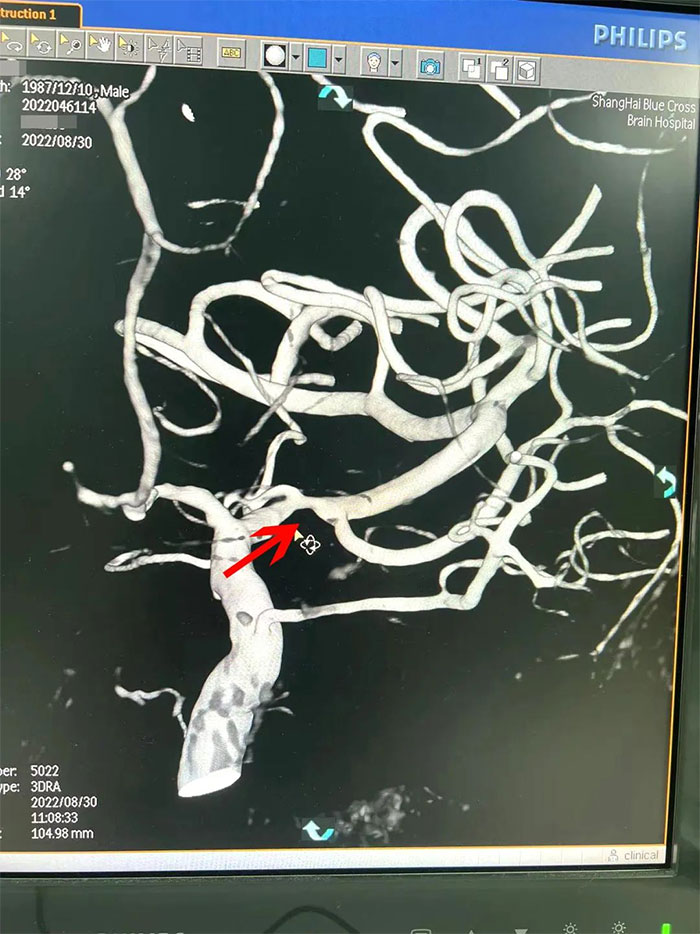

在檢查中發(fā)現(xiàn),周先生右側(cè)大腦中動脈M1段閉塞,可見煙霧狀異常血管網(wǎng)生成;左側(cè)大腦中動脈M1段重度狹窄(約70%)。符合煙霧病的典型影像學(xué)特征。

▲右側(cè)大腦中動脈M1段閉塞,左側(cè)重度狹窄

煙霧病又名Moyamoya病,腦底異常血管網(wǎng),是一組以Willis環(huán)雙側(cè)主要分支血管(頸內(nèi)動脈虹吸段及大腦前、中動脈,有時也包括大腦后動脈)起始部慢性進行性狹窄或閉塞,繼發(fā)出現(xiàn)側(cè)支異常的小血管網(wǎng)為特點的腦血管病。因腦血管造影時,呈現(xiàn)許多密集成堆的小血管影,似吸煙時吐出的煙霧而得名。